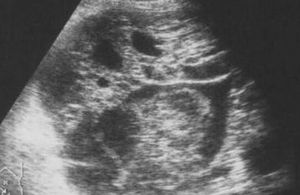

Phyllod carcinoma

Mammary Gland

Phyllod